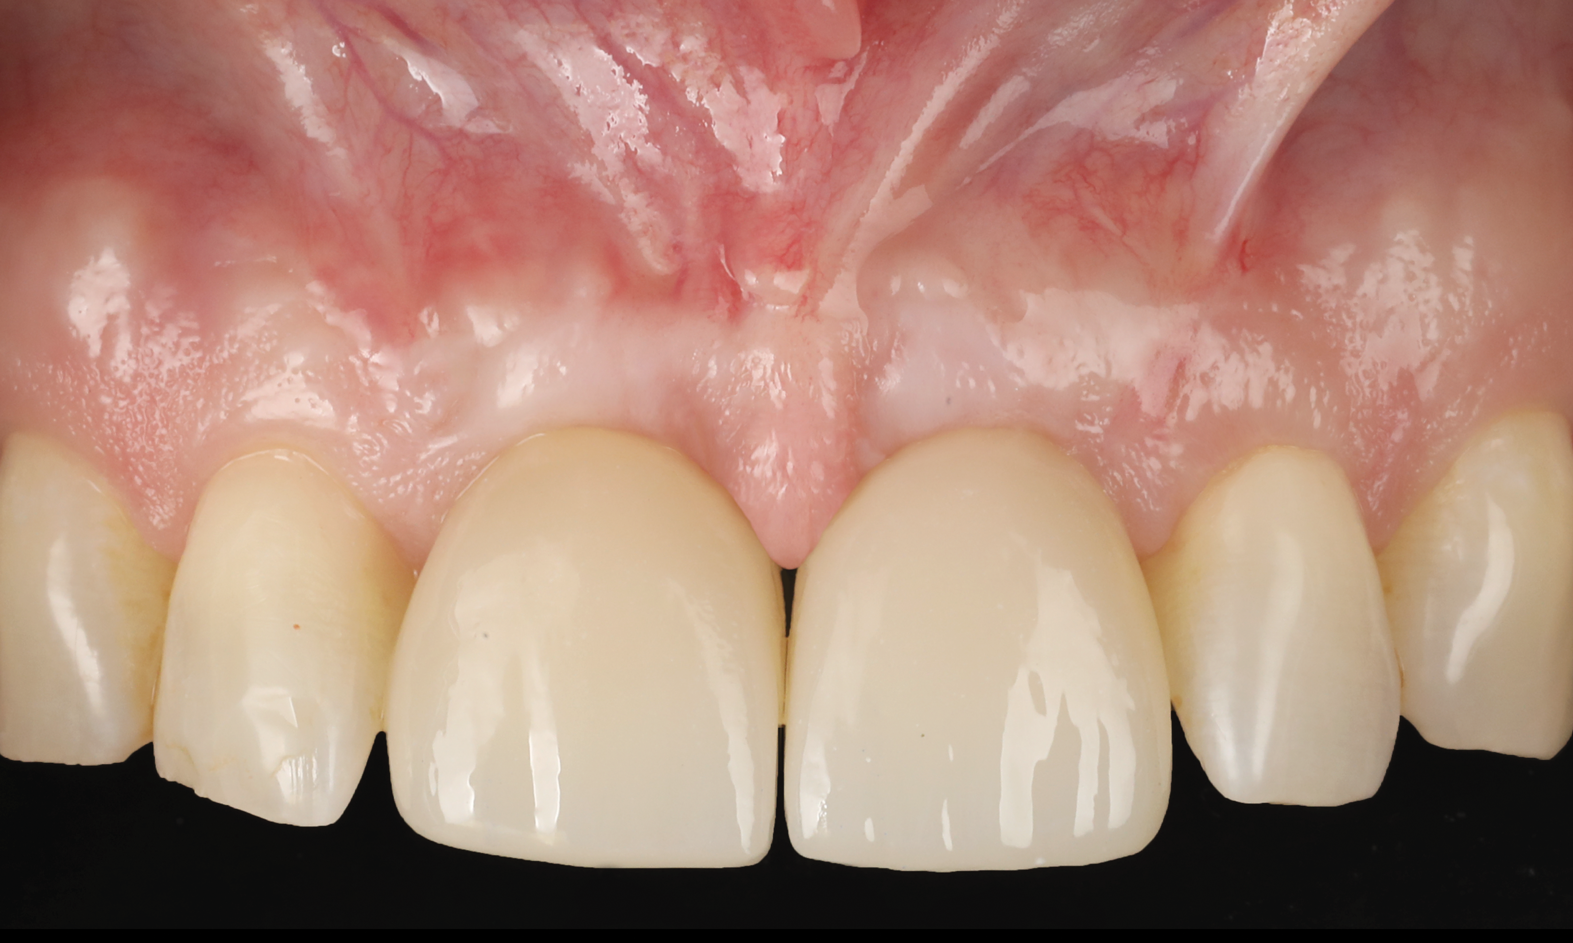

A 46-year-old systemically and periodontally healthy woman presented to the Graduate Periodontics Clinic at the University of Michigan School of Dentistry with the chief complaint of poor esthetics of her smile due to two dental implants (Nos. 8 and 9) showing their metal components (Figure 1). The patient reported that the implants had been placed 15 to 20 years previously after an accident. Clinical examination revealed that the implants had probing depths within 3 mm (facial probing depth of 3-2-3 mm for implant No. 8 and 2-2-2 mm for implant No. 9), no bleeding on probing, and no suppuration; the implants were therefore diagnosed as healthy (Figure 1 and Figure 2). The papilla between the two implants was deficient on the buccal aspect. The implants were buccally positioned, and a substantial lack of soft-tissue volume was noted.

Figure 14 depicts the final outcome at 1 year (which can be compared to the pretreatment photograph in Figure 1). Figure 15 through Figure 18 show clinical comparisons of the outcome at baseline and 1 year, while Figure 19 and Figure 20 provide an ultrasonographic characterization of the soft tissue at baseline and 1 year. The facial probing depths at 1 year were 3-3-3 mm for implant No. 8 and 3-2-3 mm for implant No. 9. The patient was highly satisfied with the esthetic outcomes and overall treatment.

Fig 1. Clinical view at presentation.

Figure 1

Fig 15. Clinical comparison of the volumetric gain obtained with the intervention, frontal views. Fig 15: Frontal view at baseline. Fig 16: Frontal view at 1-year post-treatment.

Figure 15

Fig 16. Clinical comparison of the volumetric gain obtained with the intervention, frontal views. Fig 15: Frontal view at baseline. Fig 16: Frontal view at 1-year post-treatment.

Figure 16